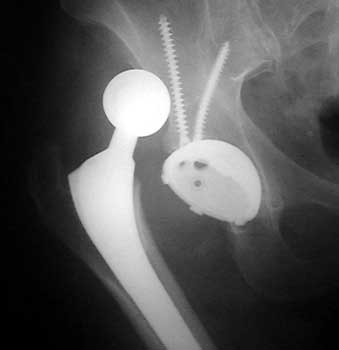

Dislocated femoral component secondary to steep acetabular cup

inclination, pre and post revision. Note constraining ring about femoral head,

which helps maintain head in cup